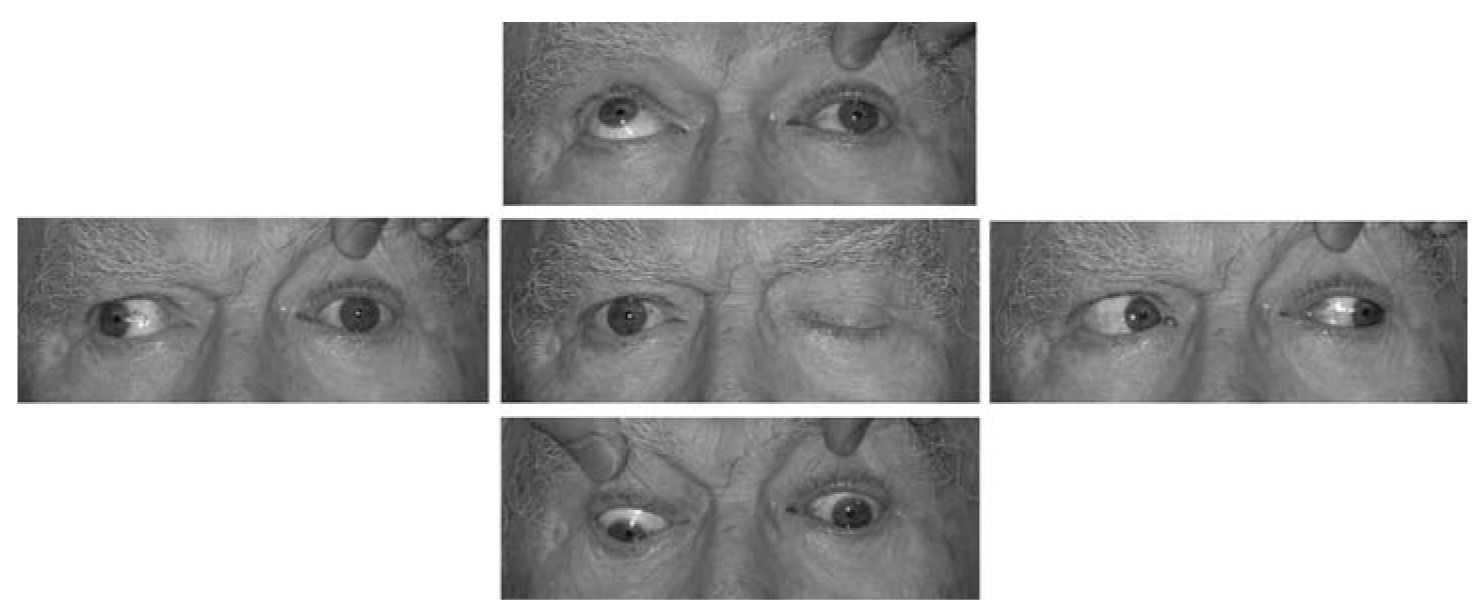

Диплопия: механизм развития и методы лечения